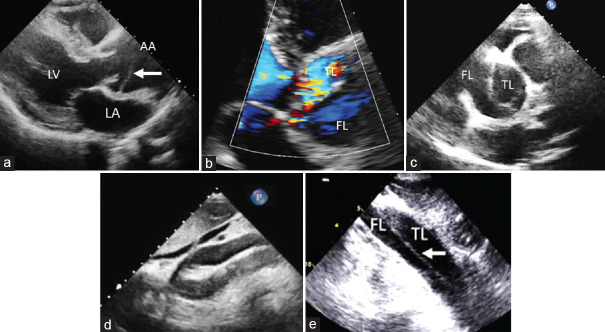

Acute aortic syndromes comprise a range of interrelated conditions including aortic dissection, intramural hematoma, penetrating atherosclerotic ulcer, and contained or not contained aortic aneurysm rupture. These syndromes are potentially life threatening; therefore, a rapid and accurate diagnosis is crucial. A new Clinical Consensus Statement on Aortic and Peripheral Vascular Disease has recently been published, and we will try to highlight the main innovations in the document.